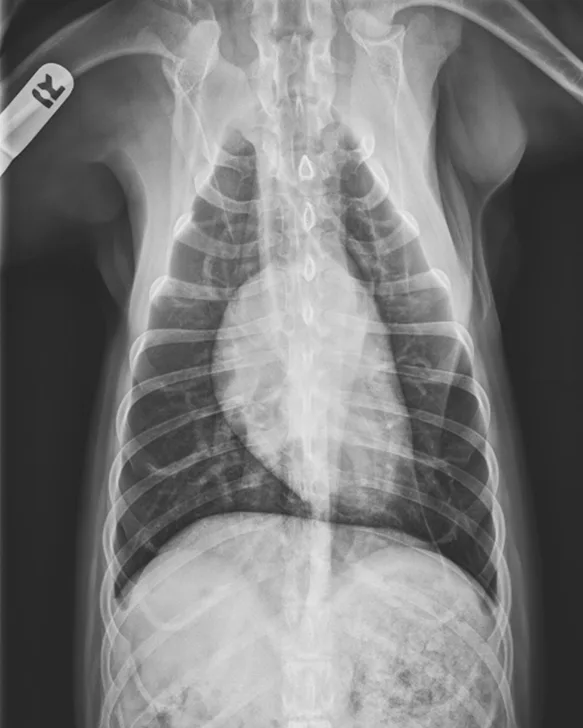

Radiograph 1 month after therapeutic initiation showing an improved bronchointerstitial pattern

At 1 month after discharge, thoracic radiography was repeated and revealed marked improvement in diffusion of the bronchointerstitial pattern (Figure 4). Prednisone was tapered over the next 6 weeks to 10 mg every other day. Intermittent coughing returned, and the dosage was increased to 10 mg once daily (0.33 mg/kg/day), which maintained clinical control. Because this regimen did not result in significant adverse effects and maintained clinical control, adjunctive or alternative anti-inflammatory medications were not prescribed.